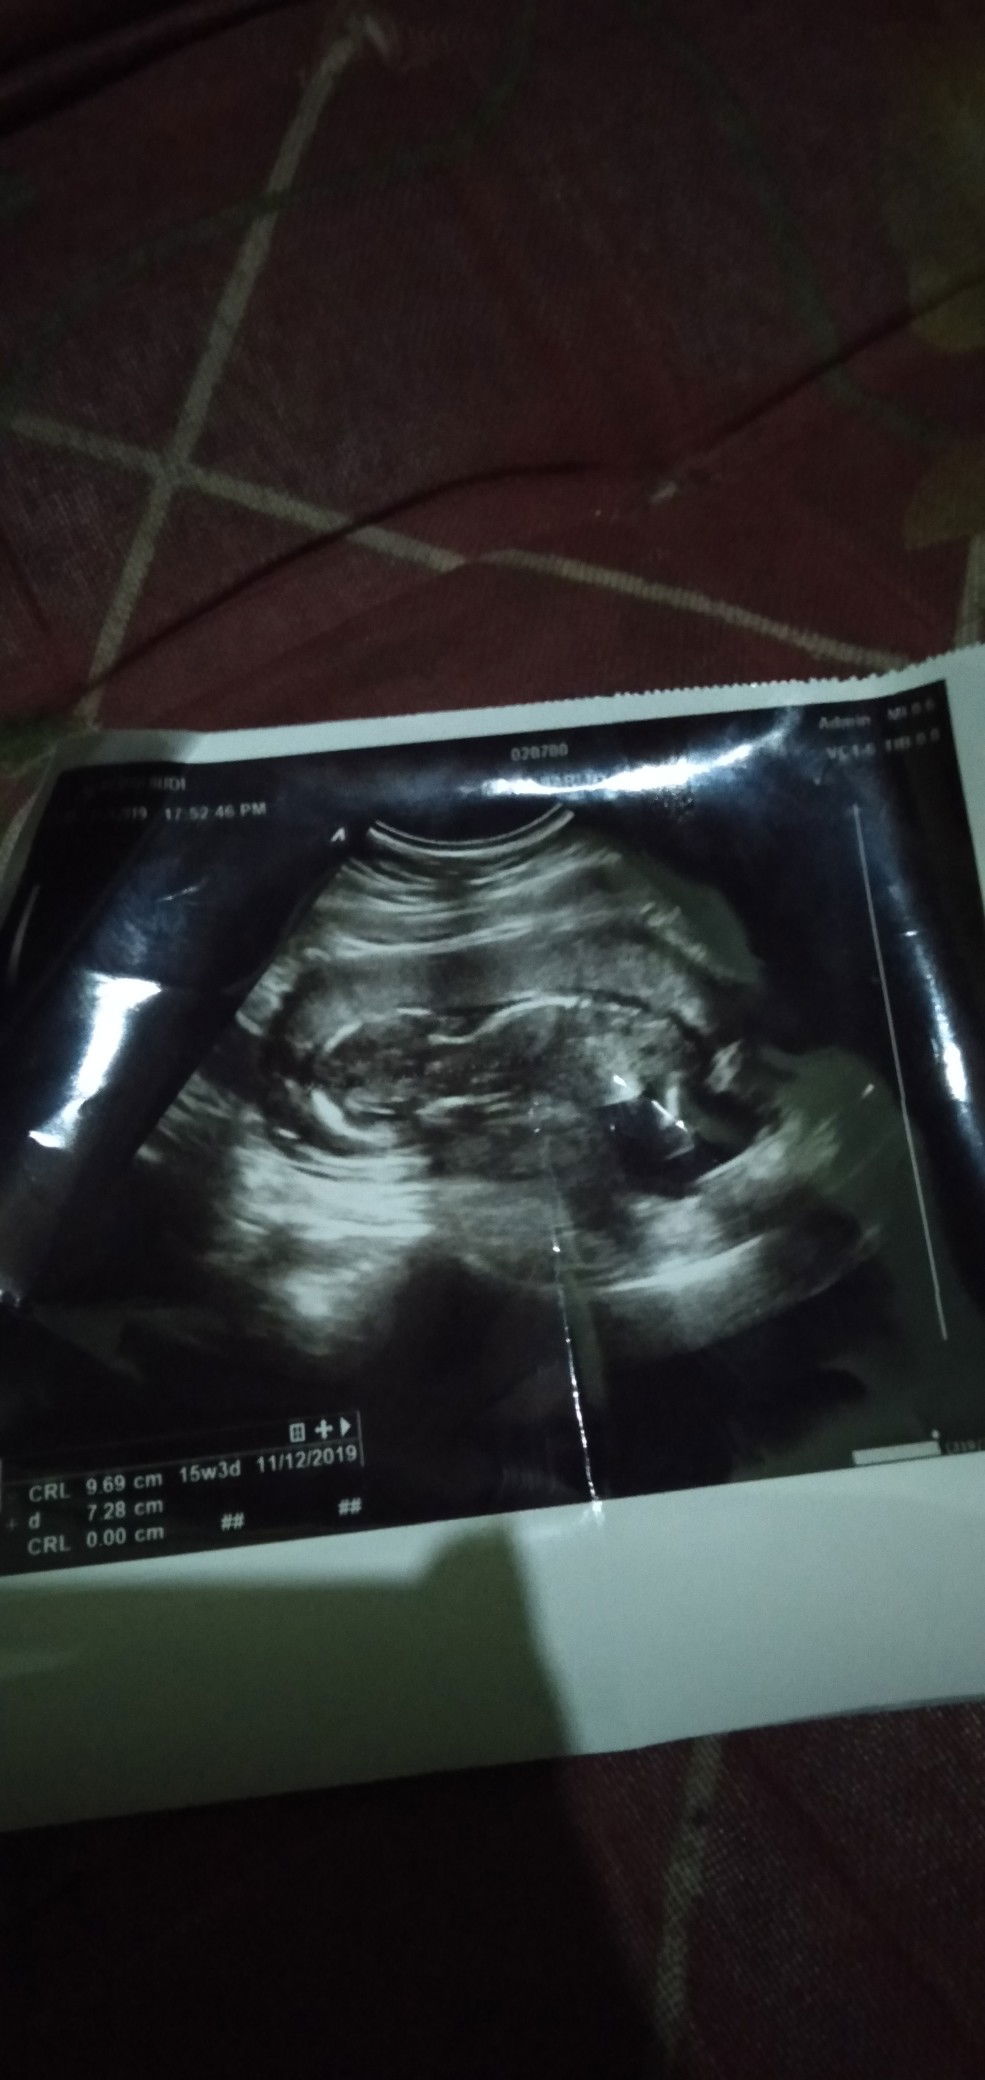

panjang baby

Ass bunda cantik?? mau nanya nih.. kemren pas usg 16 minggu panjang baby nya 9.65 cm .. Tapi aku sering lihat di artikel katanya 16 minggu itu panjang nya 11.6 cm ?? Itu gimana ya bun apa normal kyak gitu apa ada kejanggalan bun.. please info nya bun?? terima kasih bunda??